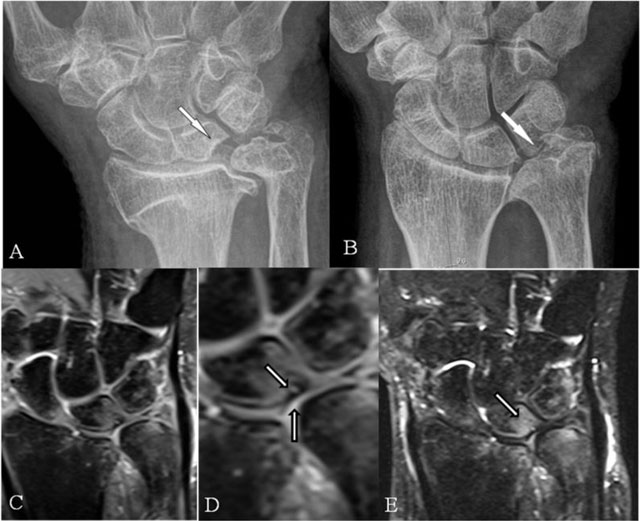

Figure 4

Ulnolunate and/or ulnotriquetral abutment. (A, B) PA plain radiographs; (C, D) Coronal SE PD-WI FS; and (E) Coronal SE T2-WI FS. (A) Ulnolunate abutment with a sclerotic defined impression at the ulnar side of the lunate bone. (B) Ulnotriquetral abutment with sclerotic bordered neoarticulation. (C–E) Ulnolunate abutment with chondromalacia at the ulnar border of the lunate bone (D, vertical arrow), subchondral cyst (D, oblique arrow), and bone marrow oedema centered at the ulnar side of the lunate bone (E).